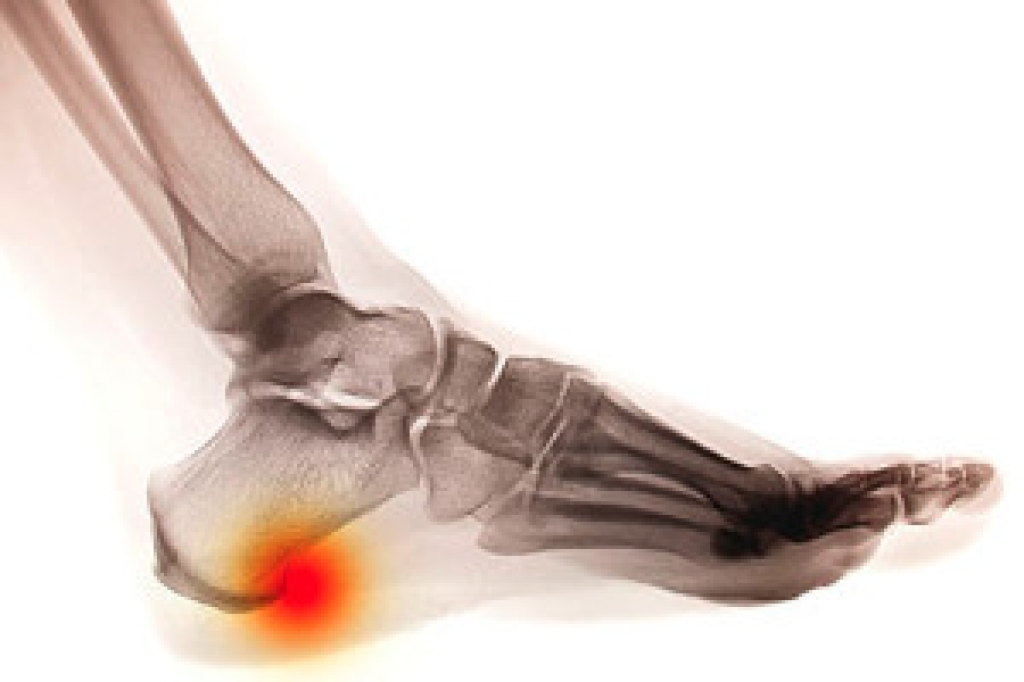

A corn can form on different parts of the foot as a result of excess friction. It is defined as a hard, thickened area, and will typically cause severe pain and discomfort. If the shoes that are worn do not fit properly, a corn may form on the inside of the pinky toe. Relief may be found if a pad is worn over the affected area. Additionally, it may help to soak the affected foot in warm water, as this may aid in softening the corn. Afterward, a pumice stone can be used in gently filing the corn to remove any dead skin. When toenails are properly trimmed, pressure may be avoided from the nail touching the skin, and this may help to prevent corns from developing. If you are afflicted with corns, it is suggested that you seek the counsel of a podiatrist who can assist you in choosing the proper treatment.

Corns are thickened areas on the skin that can become painful. They are caused by excessive pressure and friction on the skin. Corns press into the deeper layers of the skin and are usually round in shape.

Although most corns slowly disappear when the friction or pressure stops, this isn’t always the case. Consult with your podiatrist to determine the best treatment option for your case of corns.